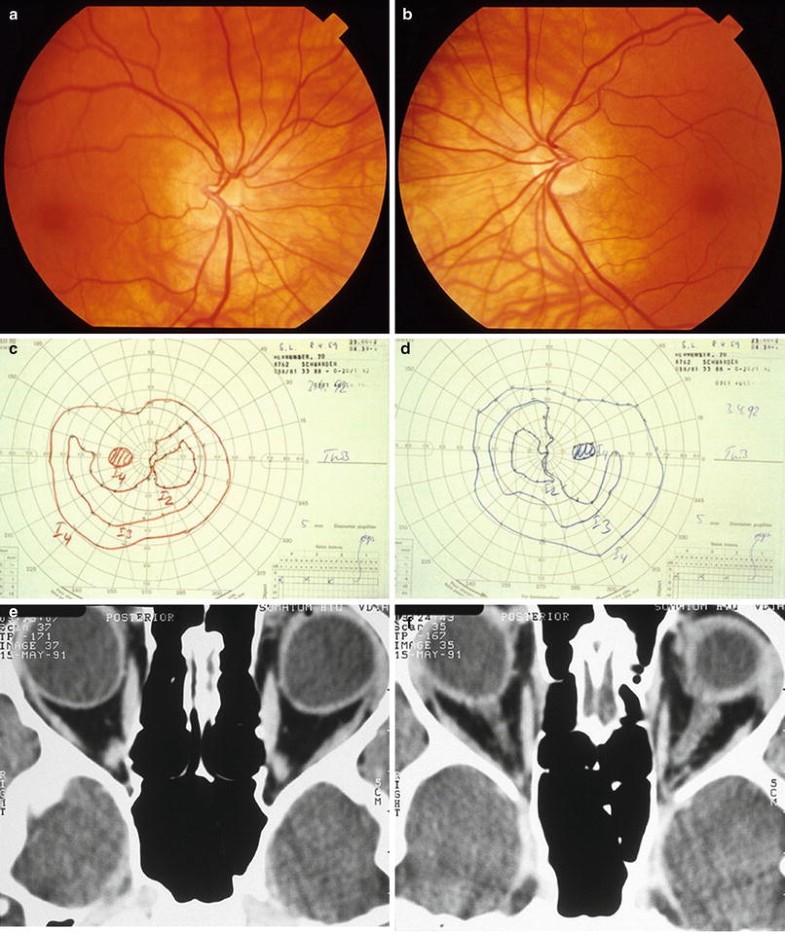

Congenital tilted disc syndrome. (a, b) Optic discs appear obliquely oval. There is elevation of superonasal discs and posterior displacement of inferonasal disc. Note subtle inferonasal peripapillary crescent, albinotic appearance of inferonasal retina, and situs inversus of vessels as they emerge from disc. (c, d) Goldmann visual field of right eye demonstrates superotemporal visual field defect confined to midperipheral isopter that does not respect horizontal meridian. (e, f) Axial computed tomography (CT) scan showing “tilted eyeballs”, with posterior protrusion of both globes (Courtesy of Klara Landau, M.D.).

Familiarity with tilted disc syndrome is crucial for the ophthalmologist because affected patients may present with bitemporal hemianopia or optic disc elevation that simulates papilledema [10, 46]. The bitemporal hemianopia in affected patients, which is typically incomplete and confined primarily to the superior quadrants, represents a refractive scotoma, secondary to regional myopia localized to the inferonasal retina. Unlike the visual field loss from chiasmal lesions, the field defects seen in tilted disc syndrome fail to respect the vertical meridian on careful kinetic perimetry. Furthermore, the superotemporal depression is selectively confined to the midsize isopter, while the large and small isopters remain fairly normal due to the marked ectasia of the midperipheral fundus. Repeat perimetry after addition of a −4.00 lens often eliminates the visual field abnormality, confirming the refractive nature of the defect. In some cases, retinal sensitivity may be decreased in the area of the ectasia, and the defect persists to some degree despite appropriate refractive correction [401].